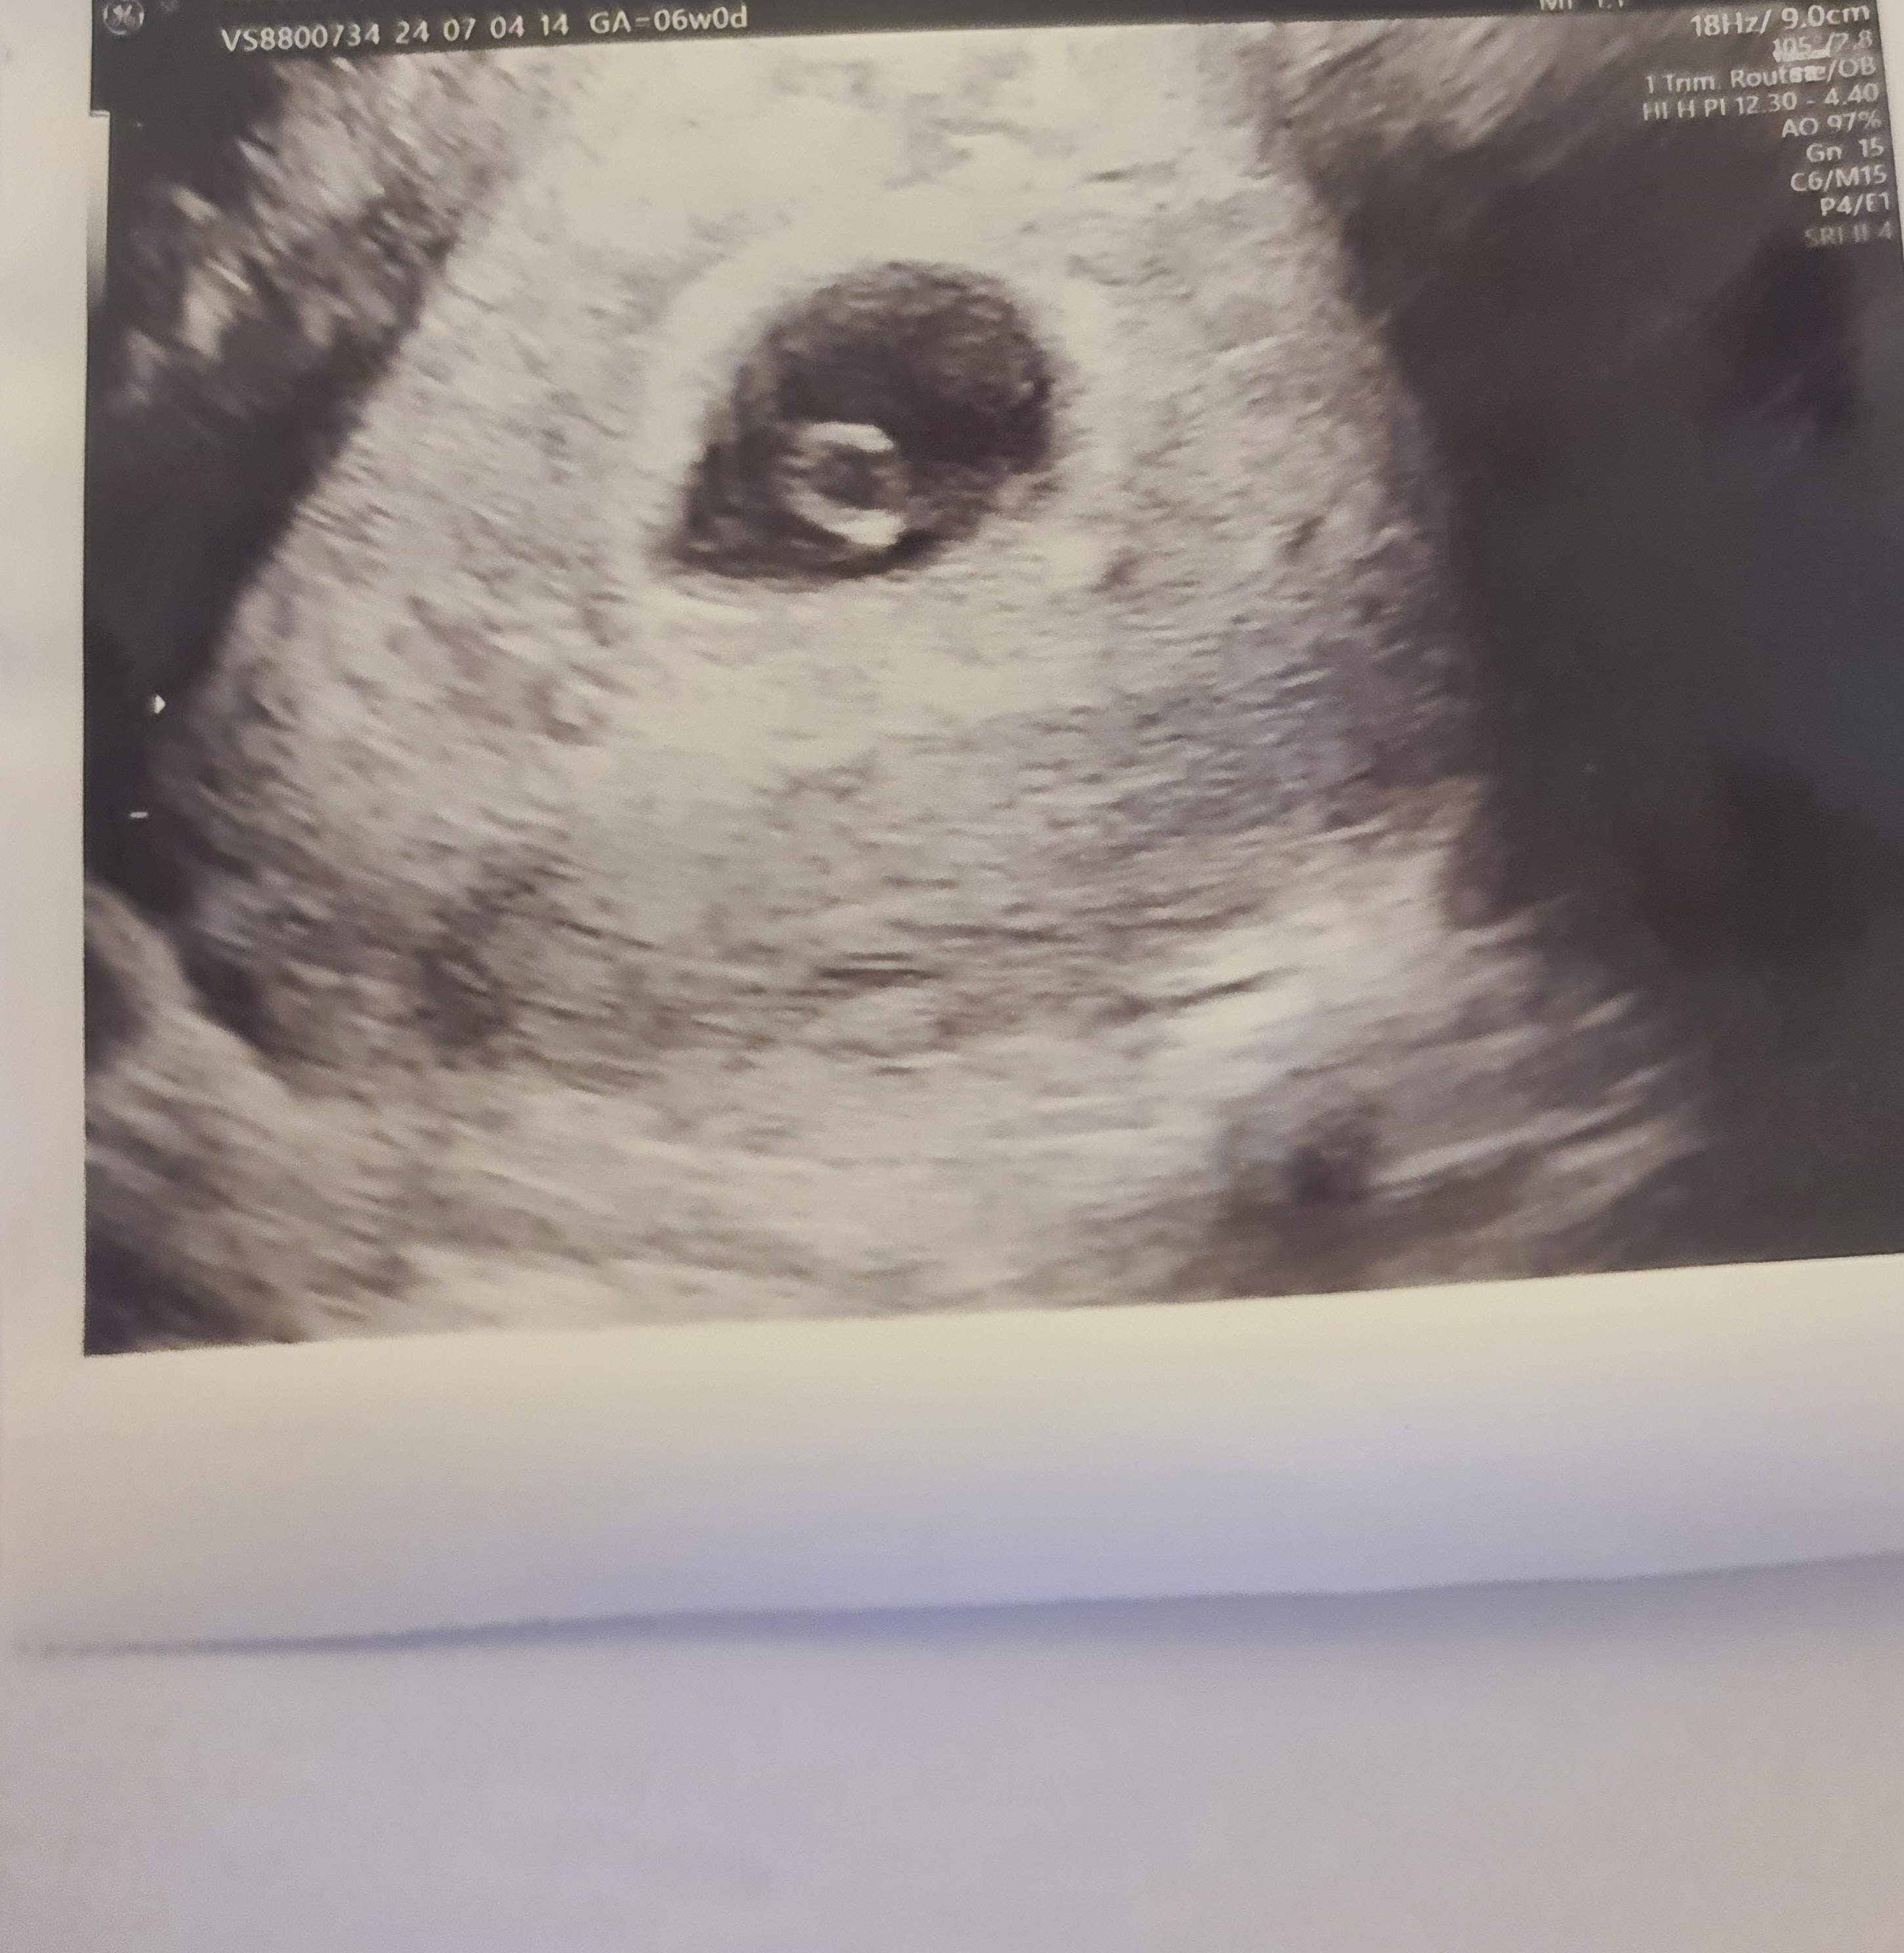

Pokażesz swoje zdjęcie usg które dostałaś?(jeśli chcesz oczywiście) Co na nim widać?